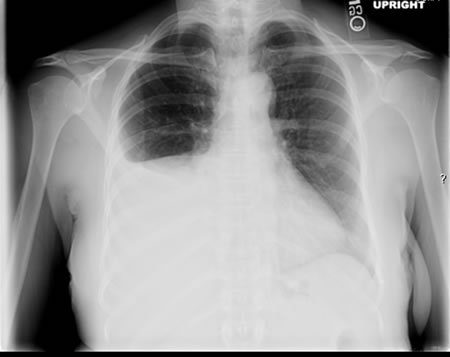

Em indivíduos imunocompetentes é quase sempre anormal. Apresenta-se tipicamente como opacidades fibronodulares nos lobos superiores com ou sem cavitação. O padrão atípico inclui opacidades nos lobos médio e inferior, linfadenopatia hilar ou paratraqueal e/ou derrame pleural.[Figure caption and citation for the preceding image starts]: Tuberculose pulmonar com cavitaçãoDo acervo pessoal de David Horne e do Dr. Masahiro Narita; usado com permissão [Citation ends].

[Figure caption and citation for the preceding image starts]: Opacidades no lobo inferior direito em um paciente com tuberculose pulmonar e diabetesDo acervo pessoal de David Horne e do Masahiro Narita; usado com permissão [Citation ends].

[Figure caption and citation for the preceding image starts]: Derrame pleural no lado direitoDo acervo pessoal de David Horne e do Masahiro Narita; usado com permissão [Citation ends].